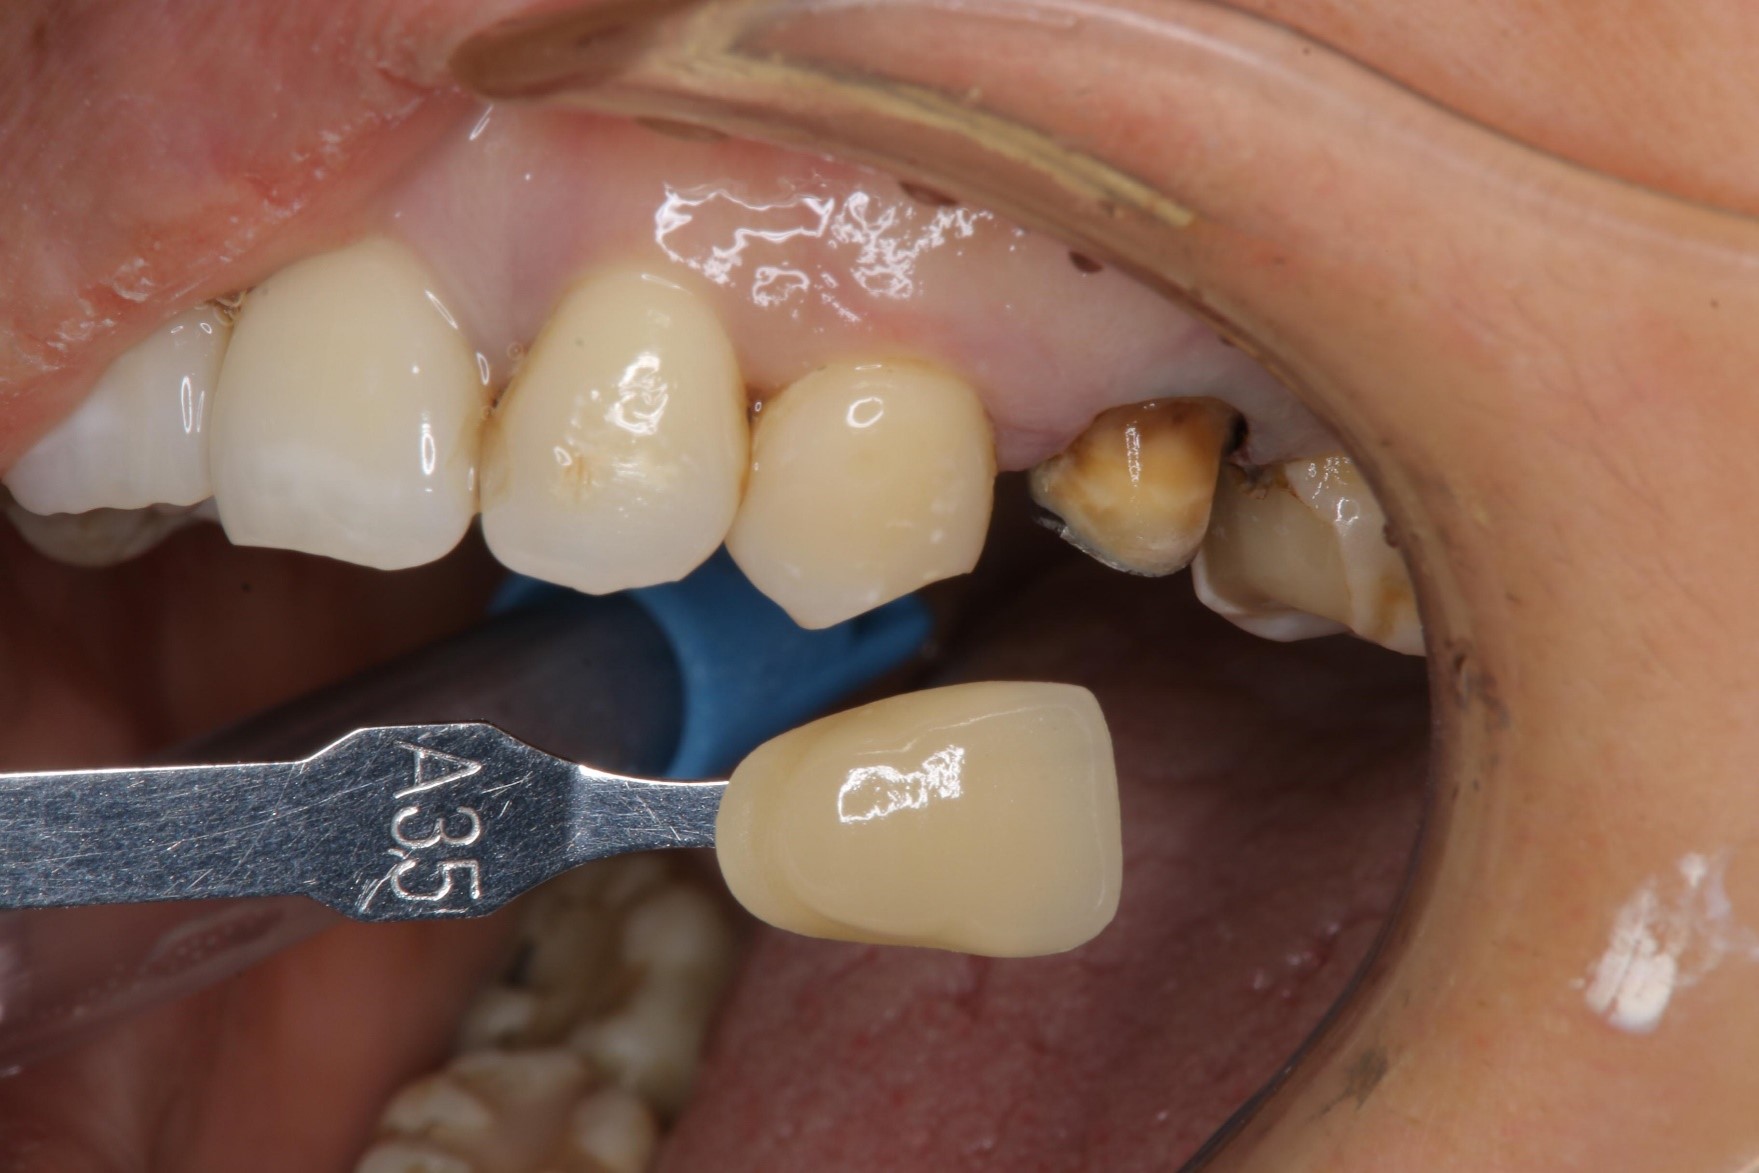

照相比色

上面弓、上咬合器